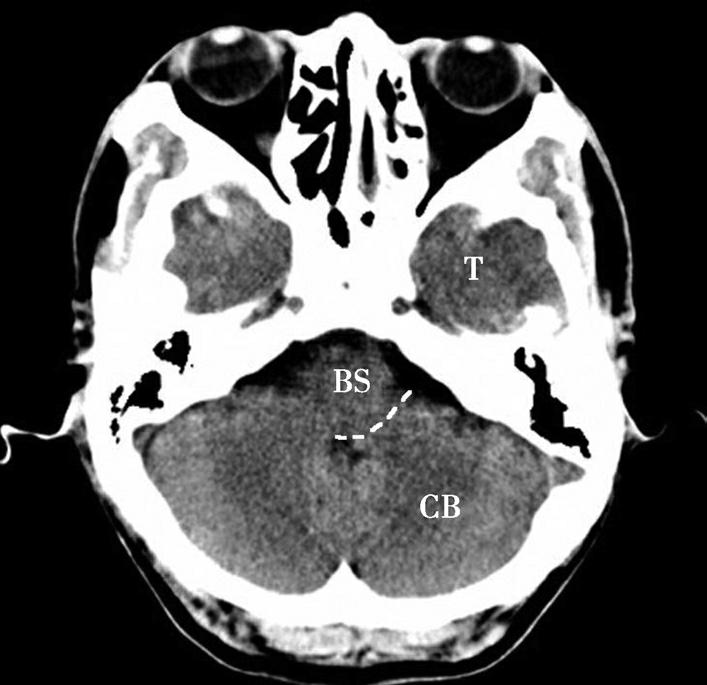

重要结构:脑桥小脑角池、脑桥、小脑、颞骨岩部尖(图1-2-5~图1-2-7)。

图1-2-7 脑叶划分示意图

CB.小脑;BS.脑干;T.颞叶

蝶骨体占据层面中部,内部可见蝶窦,中间有骨性分隔。蝶骨体前方正中为鼻中隔,鼻中隔两侧为蜂窝状含气骨性腔隙,即筛窦,筛窦前方为鼻骨。筛窦两侧可见两侧对称的圆形眼球断面位于眼眶内,眼球壁呈厚薄均匀的环状,称为眼环。玻璃体位于眼环内呈均匀低密度影,晶状体位于玻璃体前方,呈双凸透镜状高密度影,眼球后方为锥体形的眶脂体,其内正中可见视神经通行,眶内侧壁与筛窦间隔以菲薄的纸板,眶外侧壁由额骨眶突和蝶骨大翼构成,内、外直肌紧贴眶壁走向眶尖,视神经管位于眶尖。位于蝶窦两侧的有颞叶、颞骨鳞部及颞骨外侧的颞肌。蝶窦后方为斜坡,斜坡后外侧为颞骨岩部尖,后外方为乳突,其内可见乳突小房呈蜂窝状,岩部的内后缘可见两侧对称的内听道,其内第Ⅶ、Ⅷ对脑神经CT上无法分辨,听神经瘤常伴有内听道的扩大(图1-2-8)。内听道后外方的骨性空腔为中耳鼓室。枕骨斜坡及岩骨后方为颅后窝,脑桥位于其前部,脑桥后方可见第四脑室,其后方为小脑蚓部。小脑半球以小脑中脚与脑桥相连,脑桥与斜坡之间为桥前池,其向两侧延伸的部分呈三角形,两侧对称,位于脑桥、小脑中脚及岩骨之间,称为脑桥小脑角池。位于脑桥小脑角池的常见病变有听神经瘤、三叉神经瘤、脑膜瘤和胆脂瘤等(图1-2-9)。